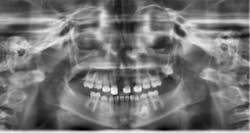

Upon clinical and radiographic examination, the patient presented with multiple missing permanent teeth (figures 3, 4a, and 4b). Tooth No. 8 was malpositioned and slightly mobile. Her mandibular dentition was stable and intact, although mostly deciduous (figure 5). Upon further questioning, I learned that her brother had a similar condition. Taking into consideration the patient’s physical appearance and the genetic similarity to her brother, I discussed with her parents the need to obtain a medical diagnosis through genetic testing.